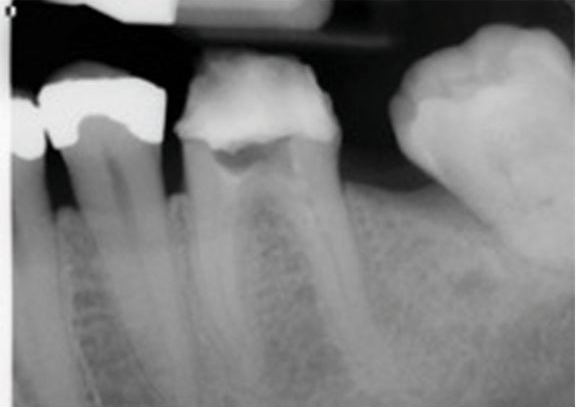

(5.) Preoperative radiograph of tooth No. 19 following a pulpectomy procedure that was complicated by an intraoperative furcal perforation.

Figure 5

(6.) Postoperative radiograph showing immediate perforation repair using MTA followed by complete obturation.

Figure 6